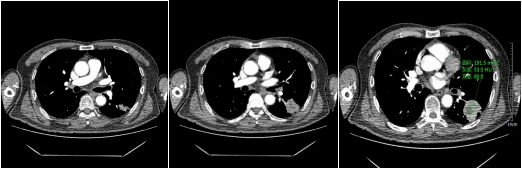

动脉期

静脉期